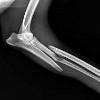

Radiography of limb bones.

Рентген кости. Набор методов радиологического изучения морфологии костно-мышечной системы в нормальных и патологических состояниях. Благодаря высокому содержанию солей кальция и фосфора костная ткань хорошо контрастирует на фоне окружающих мягких тканей. Рентгенологическому исследованию могут быть подвергнуты различные части скелета: кости черепа, грудной клетки, верхних и нижних конечностей, таз. Рентген используется для диагностики переломов костей и контроля их лечения, инфекционных воспалительных процессов, остеопороза, первичных и метастатических опухолей костей, плоскостопия Для большей информативности рентгеновские снимки костей выполняются в двух проекциях, часто с функциональными пробами.

Рентгенография костей широко используется в травматологии для диагностики переломов, определения типа поражения, направления и степени смещения осколков (необходим для активной репозиции, правильного наложения скелетного вытяжения и планирования переломов). хирургии), а также для оценки эффективности лечения. Рентгенография костей назначается при поступлении, после репозиции, применении аппарата Илизарова, фиксации пластинкой, шурупами, спицами и другими металлическими конструкциями. Кроме того, рентгеновские снимки костей выполняются с циркулирующей гипсовой повязкой (чтобы не было новых смещений) перед удалением гипса и скелетного вытяжения (для определения степени консолидация перелома).

Рентгенологическое исследование костей является очень информативным методом для исследования костных структур, но не позволяет детально изучить состояние окружающих мягких тканей: волокон, мышц и сухожилий. Травма скелета, связанная с повреждением мягких тканей, таким как перелом кости в сочетании с разрывом сухожилия, и рентгенография костей может потребовать МРТ пораженного сегмента конечности, что позволяет визуализировать образование мягких тканей. При некоторых патологических состояниях информативность костного рентгеновского излучения снижается. Следовательно, перелом шейки бедра без смещения у пожилых пациентов с остеопорозом на рентгенограммах иногда отсутствует или только плохо виден. В таких случаях для уточнения диагноза после рентгенологического исследования костей также назначается КТ кости. КТ и МРТ делают обследование более дорогим и, следовательно, проводятся с достаточными доказательствами.